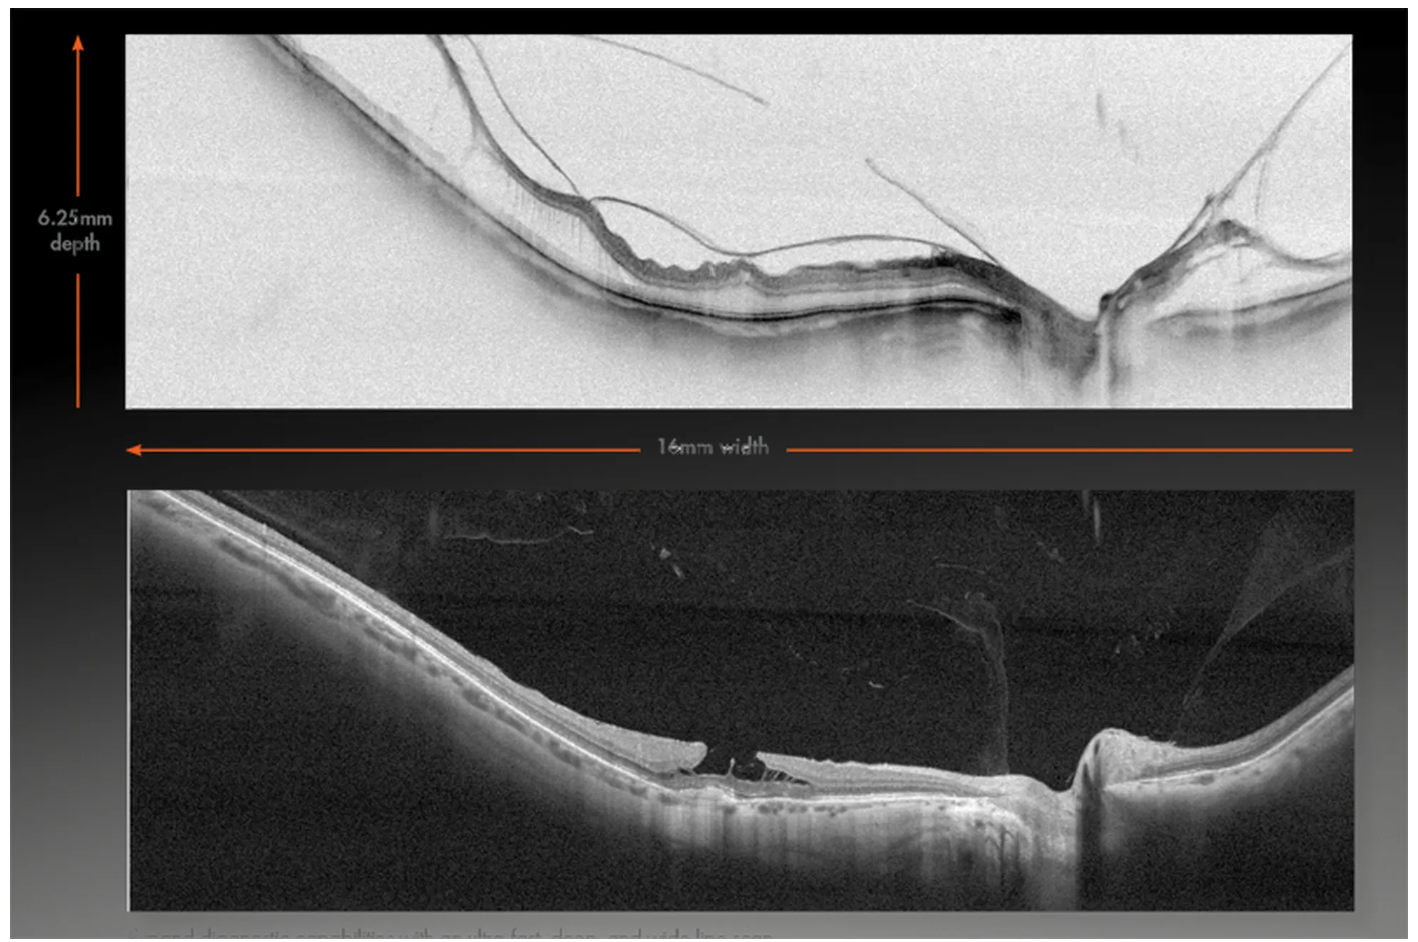

- Диапазон сканирования в режиме ангио-ОКТ — от 3х3 до 18х18 мм;

- Размер зоны сканирования в аксиальном направлении — 6,25 мм;

- Полноразмерное сканирование передней камеры;